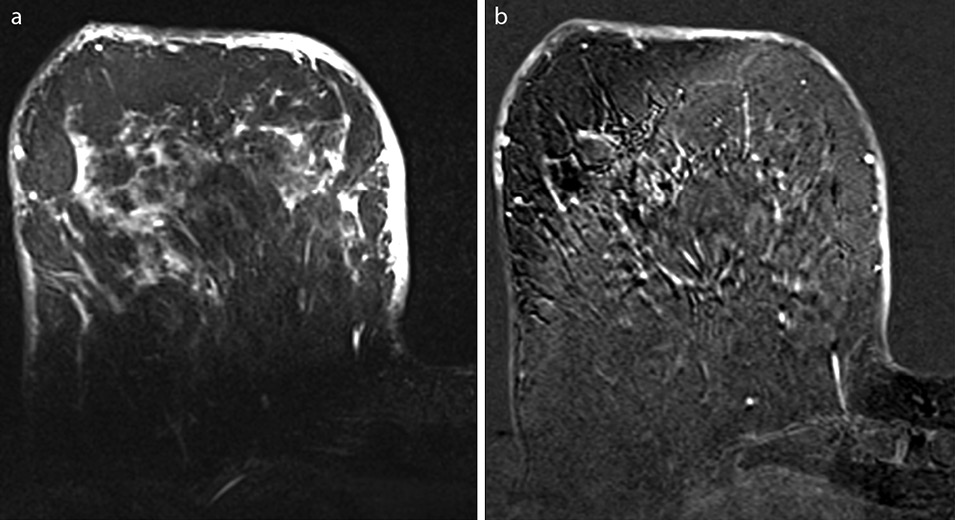

Среди всех методов визуализации в диагностике локального и диффузного отека кожи маммография характеризуется наиболее высокой эффективностью за счет возможности анализа симметричных зон «суммационного» изображения органа. При этом основным признаком отека кожи является ее утолщение (рис. 1). С помощью ультразвукового исследования молочных желез также возможно визуализировать отек кожи за счет утолщения и активного кровоснабжения кожного покрова (рис. 2). Но данный метод субъективен и обладает низкой результативностью в выявлении локального отека кожи. Роль магнитно-резонансной томографии молочных желез в решении этого вопроса незначительна (рис. 3), и поэтому этот вид визуализации не может использоваться для дифференциальной диагностики злокачественной и доброкачественной природы отека (уровень доказательности 1b, уровень рекомендаций A) [4].

Рис. 3. Магнитно-резонансная томограмма в режиме Т2 (a) и Т1-постконтрастном (b). Определяются утолщение кожи и высокий сигнал на Т2-взвешенном изображении и на постконтрастной томограмме.